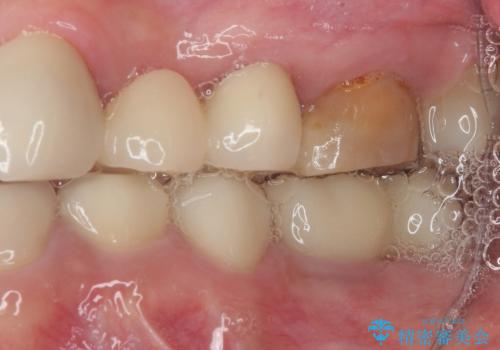

- 冷たいものがしみることがあるとのことで来院された患者様です。

銀歯の下にまでむし歯が及んでおり、レントゲン写真からも神経組織に迫っている状態が確認されました。

稀に冷たいものがしみる程度で、術前診査では神経を全て取る可能性は低いと予想されましたが、一部切除する可能性が高いことを伝えた上で治療を行うこととしました。

銀歯や欠損が大きいことから、虫歯治療後はオールセラミッククラウンによる補綴治療を行うこととしました。